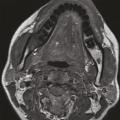

Bilan d’imagerie et orientation diagnostique des cancers des voies aérodigestives supérieures

Les voies aérodigestives supérieures (VADS) constituent la partie haute des systèmes respiratoire et digestif. Elles sont constituées de muqueuses, soutenues par des éléments musculaires complexes et des structures osseuses et cartilagineuses dont l’analyse fine est nécessaire afin de déterminer l’extension des lésions qui s’y…